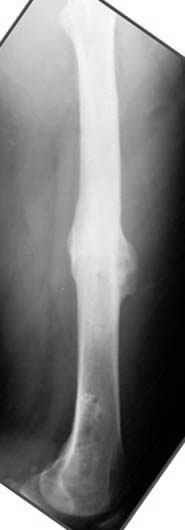

Несколько снимков из моей коллекции, чтобы разьяснить, почему мы до сих пор делаем различные варианты остеотомии.

На рисунке N1 предоперационный план лечения ложного сустава шейки бедра- линия ложного сустава, угол и направление введения импланта, клиновидная остеотомия в градусах и миллиметрах, второй снимок после коррекции, расчет, на сколько удлиняется конечность и размеры импланта;

N3 рисунок окончательный снимок, после операции моя рентгенограмма должен выглядеть примерно как эта картина. На N4 снимке клин перед удалением; N5 послеоперации 3 нед.; N6 окончательная рентгенограмма.

(доложен в Ст. Петербурге 2003 и в Москве 2004)

пластическая модель; и коррекция бедра аппаратом Илизарова.